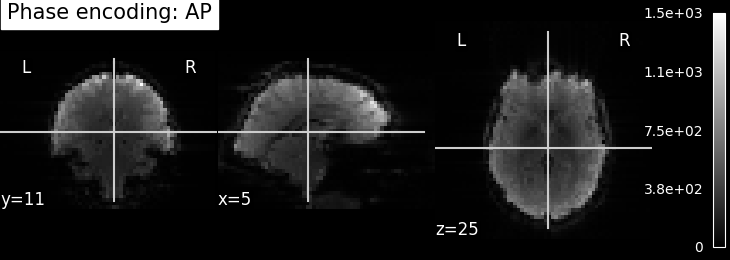

EPI field mapping

EPI images can be utilized to approximate a field map by acquiring two volumes with opposite phase encoding directions. The difference in distortion between these two acquisitions is then utilized in a least squares algorithm to estimate the field map. Although the resulting field map may exhibit some artifacts, as demonstrated in the following images, it is still sufficient to correct for distortion to some extent.

To perform this step, FSL command line tools such as TOPUP, FUGUE, and FLIRT are employed for the analysis. These tools enable the processing and correction of distortion in the EPI images, contributing to improved image quality.